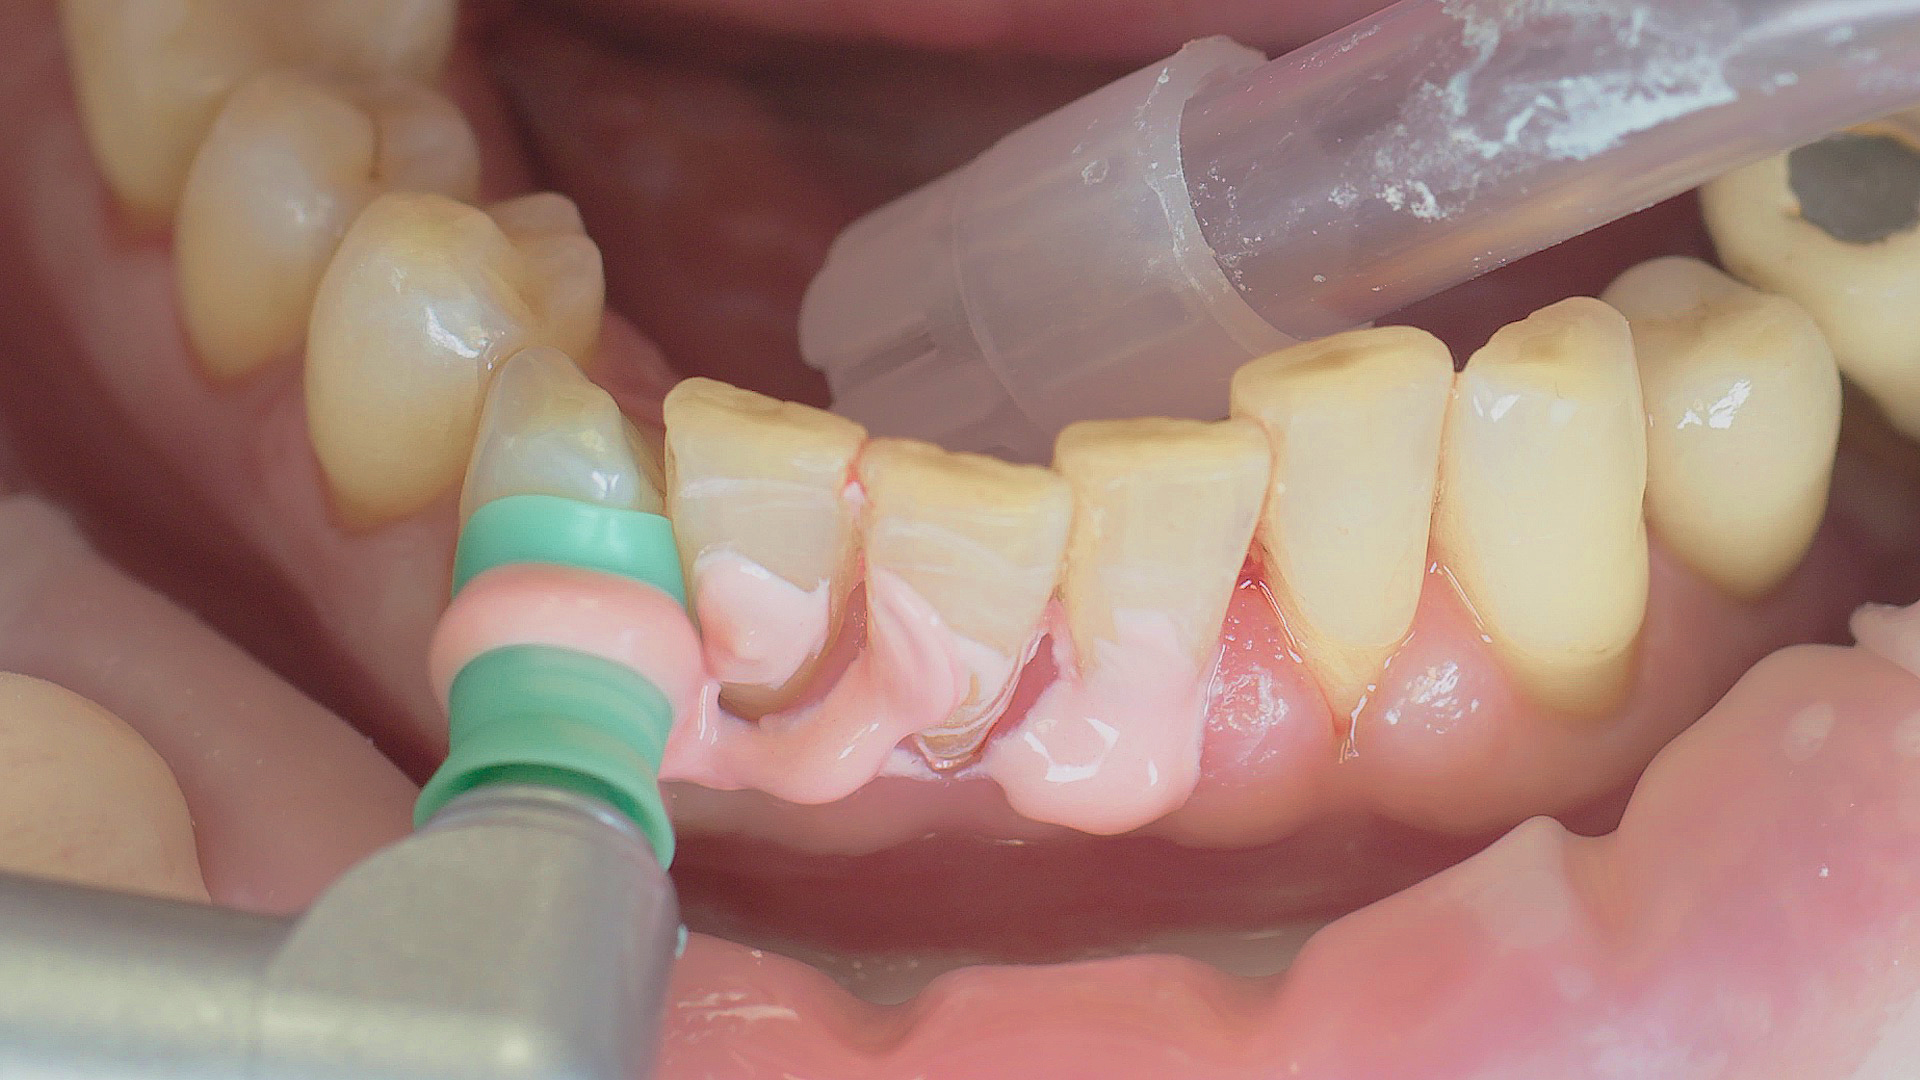

In the periodontal aftercare subsequent to implantation, soft (biofilm) and hard coatings are regularly professionally and mechanically removed.[16, 17] In the subgingival and supragingival areas, ultrasonic devices are generally used for this (Fig. 4), in combination with manual instruments where necessary. Alternatively, subgingival air polishing can be used in combination with periodontal attachments and powders.[18]

At-home oral hygiene should be carefully tailored to the new prosthesis and the patient accordingly instructed on this.[34] In combination with professional biofilm management, good preventative efficacy can be achieved in this way.[35] The risk of peri-implantitis decreases from 43.9 per cent (no recall) to 18.0 per cent if a patient receives a recall appointment carried out carefully each year, in other words by more than half.[36] Ultrasonic systems with special instruments that do not affect the materials are suitable for this, such as those made of PEEK (Fig. 5), or appropriate manual instruments.[37]